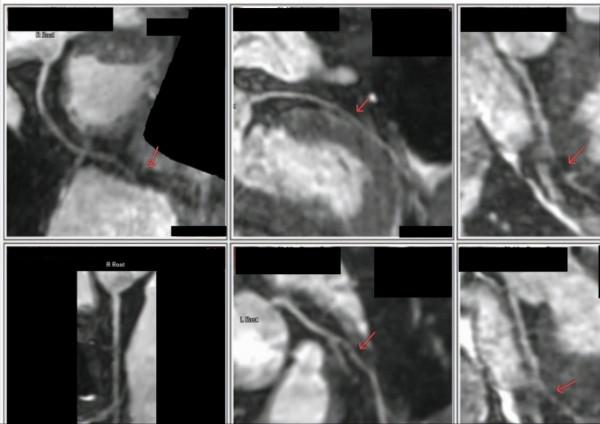

▲王先生冠脈成像圖

經醫師評價,心臟MRI示心臟收縮功能正常,心腔大小正常,心肌厚度正常;

MRA冠脈成像提示左前降支中度狹窄可能,左迴旋支末梢臨床意義狹窄可能。

但前降支:中段、第一對角支見疑似中度狹窄;迴旋支:後側支見疑似臨床意義狹窄的低訊號影。